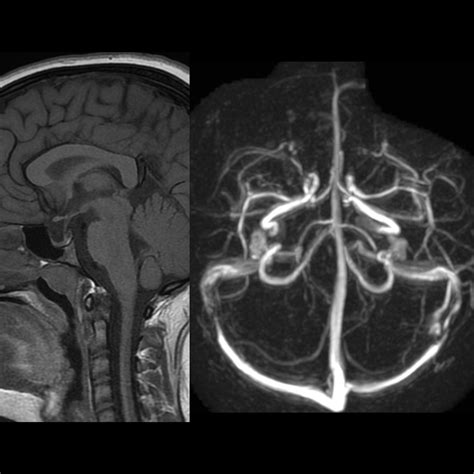

To understand this condition, we must first look at the sella turcica—a bony, saddle-shaped depression at the base of the skull that houses and protects the pituitary gland. In a typical anatomy, the sella is filled primarily by the pituitary gland itself. However, in individuals with an Empty Sella Syndrome (ESS), the sella appears "empty" on imaging results like an MRI or CT scan because it has become filled with cerebrospinal fluid (CSF).

When the condition is classified as a Partial Empty Sella, it means that the sella is only partially filled with CSF, while a significant portion of the pituitary gland remains in its expected position. This can occur due to a defect in the diaphragm sellae—the fold of dura mater that usually acts as a barrier between the brain and the pituitary gland. If this seal is weak, the increased pressure of the CSF can push into the sella, flattening the gland against the bony walls.

If a doctor suspects you have a Partial Empty Sella, they will likely start with an MRI scan, as it provides the most detailed look at the brain structure. Once the imaging confirms the finding, the focus shifts from the "empty" space to the functionality of the gland. A comprehensive evaluation usually involves: